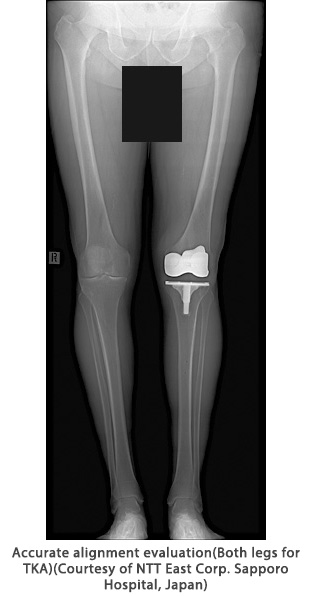

This application provides simple operation, a large imaging area, and easy-to-interpret images for efficient examination and accurate diagnosis. It is available with the Shimadzu R/F system and general radiography systems.

Long view imaging